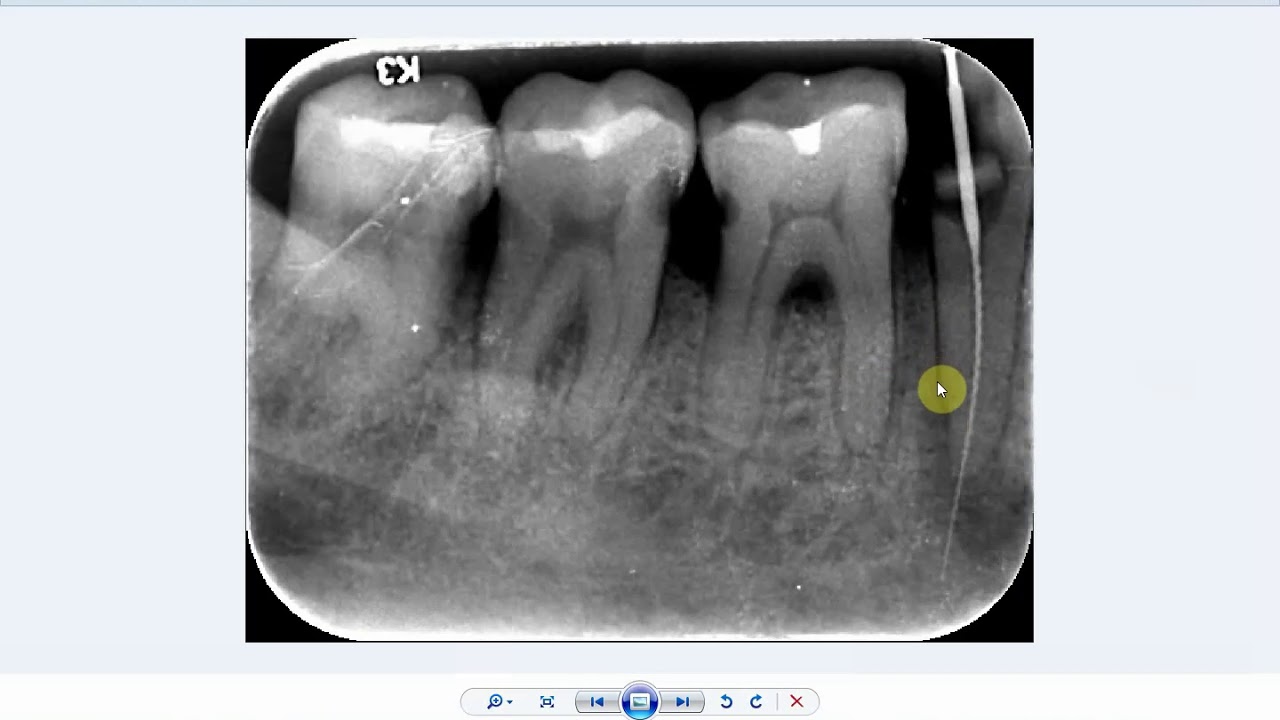

Is this the mental foramen or a periapical pathology?

Mental Foramen - Dr. G's Toothpix Definition: A foramen seen near the apex of the mandibular second premolar. It may be projected as far mesially as the first premolar and distally as the first molar. To determine if a radiolucent area seen at the apex of the second premolar is pathosis associated with the tooth or normal anatomy (mental foramen) you need to evaluate the periodontal ligament space and lamina dura.